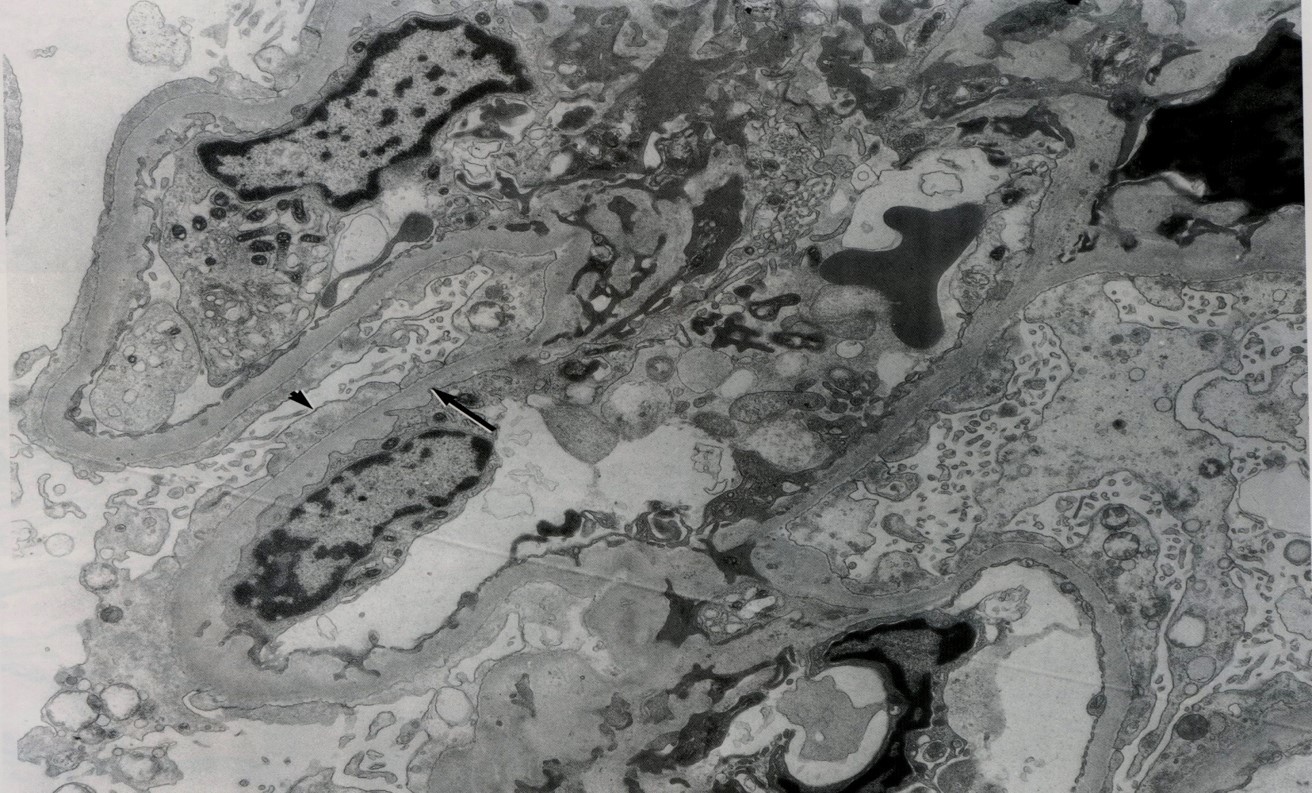

Arrow is pointing to subepithelial side with a “hump”

(to dx acute post strep GMN)

Classic case of what?:

Acute Post-Strep GMN

(sxs of nephritic syndrome)